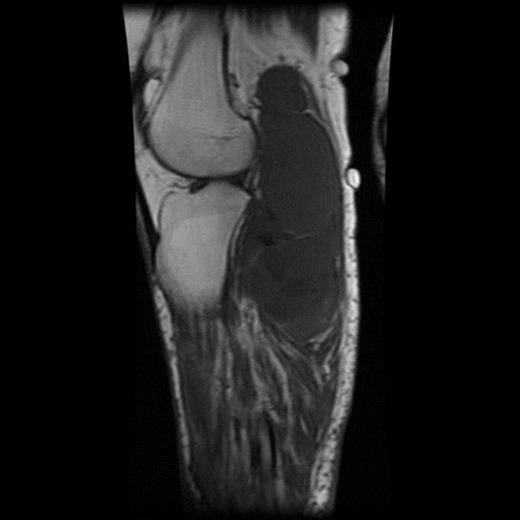

The MRI scan of the right knee (Figs 2 and 3) with gadolinium-enhancement showed a large mass lesion in the posterior aspect of the right knee extending into the popliteal fossa and into the upper third of the right leg having appearance of bursal pathology. Post gadolinium images showed evidence of circumferential rim enhancement but no internal enhancement indicating the presence of a fluid filled lesion. The mass (Figs 4 and 5) measured ∼8.39 × 6.14 × 12.72 cm and was seen between semimembranosus and biceps femoris muscles. There was no evidence of any infiltration of either the sciatic nerve or the popliteal vessels. A likely diagnosis of complicated synovial cyst with a differential diagnosis of haematoma was reported and a provisional diagnosis of Baker's cyst was established.

T1-weighted MRI image showing mass occupying whole of posterior aspect of knee extending to proximal portion of the leg.